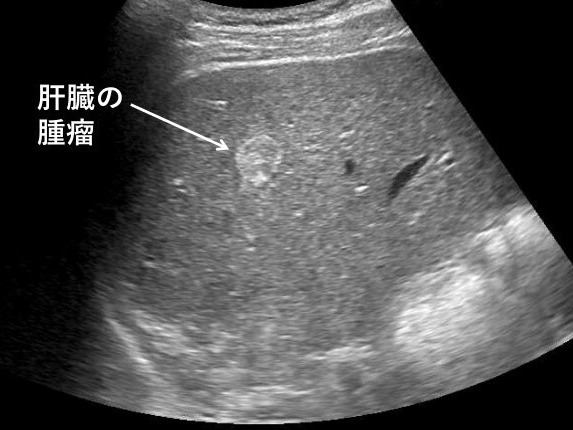

- 간암, 간종양: 실질 내부에 덩어리 유무 탐색